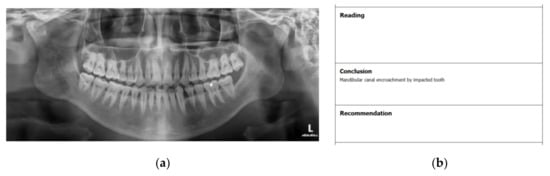

Figure 1. (a) Sample DPR image and (b) study report.